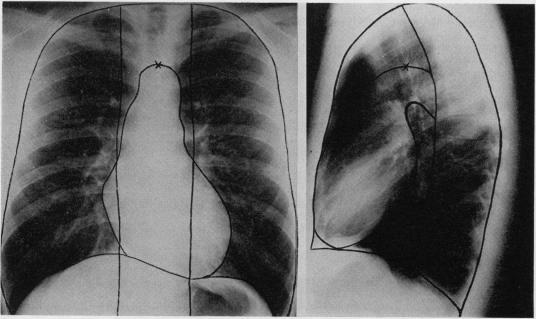

利用形状信息从胸部X光片估计肺容积。

Estimation of lung volumes from chest radiographs using shape information.

The cross-sectional shapes of the chest and its contained structures have been assessed in post-mortem anatomical sections and from computerised tomographic scans in living subjects. These shapes are described by simple equations that can be used to increase the accuracy of measuring lung volumes from chest radiographs. Radiographic estimates of total lung capacity, using the equations, were compared with plethysmographic and single-breath helium dilution measurements in 35 normal subjects. The postures commonly used for taking chest radiographs were found, on average, to decrease total lung capacity (TLC) and to increase residual volume by about 200 ml when compared with the sitting positions used for the other two measurements (studies made in 18 of the subjects). After correction for this effect, the radiographic estimates of TLC, which measure the displacement volume of the lung, exceeded the plethysmographic estimates of contained gas volume by a mean of 720 ml, which was taken as the volume of tissue, blood, and water in the lungs. The single-breath dilution estimates of TLC fell short of the plethysmographic values by a mean of 480 ml, taken as the volume of contained gas that was inaccessible to helium in 10 seconds. The tomographic studies suggested that the radiographic technique of measuring lung displacement volumes has an accuracy of +/- 210 ml. The method is rapid and simple to use and has intra- and inter-observer variabilities of less than 1% and less than 5% respectively.

已在尸检解剖切片以及活体受试者的计算机断层扫描中评估了胸部及其所含结构的横截面形状。这些形状由简单的方程式描述,可用于提高从胸部X光片测量肺容积的准确性。使用这些方程式对35名正常受试者的肺总量进行X光片估计,并与体积描记法和单次呼吸氦稀释测量结果进行比较。结果发现,与用于其他两项测量的坐姿(对18名受试者进行的研究)相比,通常用于拍摄胸部X光片的姿势平均会使肺总量(TLC)降低,并使残气量增加约200毫升。校正此效应后,测量肺移位容积的TLC的X光片估计值比体积描记法估计的所含气体容积平均高出720毫升,这被视为肺中组织、血液和水的容积。TLC的单次呼吸稀释估计值比体积描记法值平均低480毫升,这被视为10秒内氦无法进入的所含气体容积。断层扫描研究表明,测量肺移位容积的X光片技术的准确度为±210毫升。该方法快速且易于使用,观察者内和观察者间的变异性分别小于1%和小于5%。